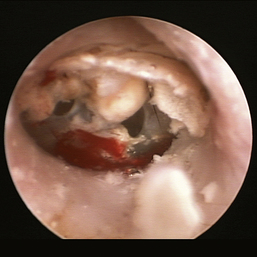

image

Figure 20-16 Ceruminal gland adenoma with blood noted in the external ear canal of a dog.